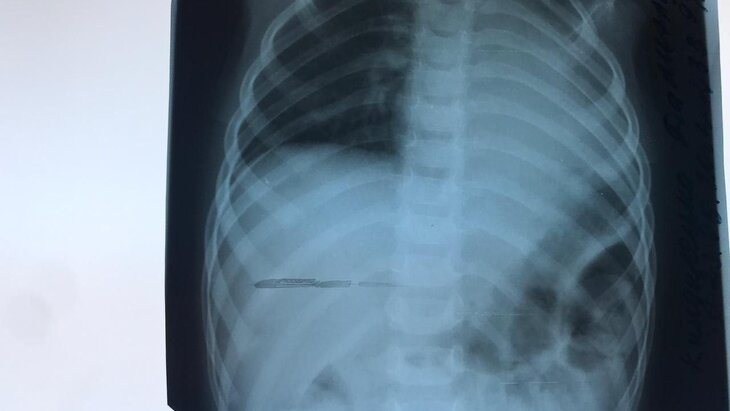

Врачи детской городской клинической больницы № 9 имени Сперанского удалили из бронха двухлетней пациентки арахис. В дыхательной системе ребенка он пробыл месяц, как передает Агентство "Москва".

"Двухлетнюю девочку с высокой температурой и кашлем госпитализировали в детскую больницу имени Сперанского. Под маской бронхита скрывалось инородное тело в левом легком, откуда его успешно извлекли хирурги клиники", – рассказали в пресс-службе Депздрава.

В ведомстве уточнили, что за месяц арахис разбух, что спровоцировало увеличение легкого. Исправить дефект удалось с помощью бронхоскопии. Ожидается, что через две недели после выписки пациентку осмотрят повторно.